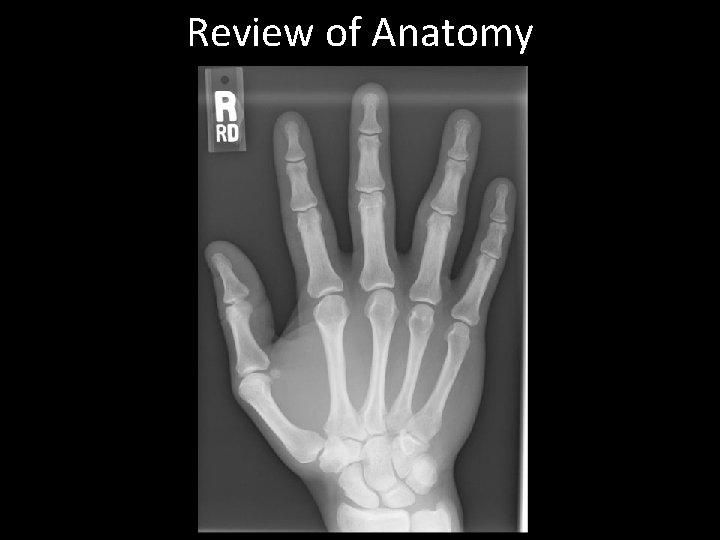

Review of Anatomy